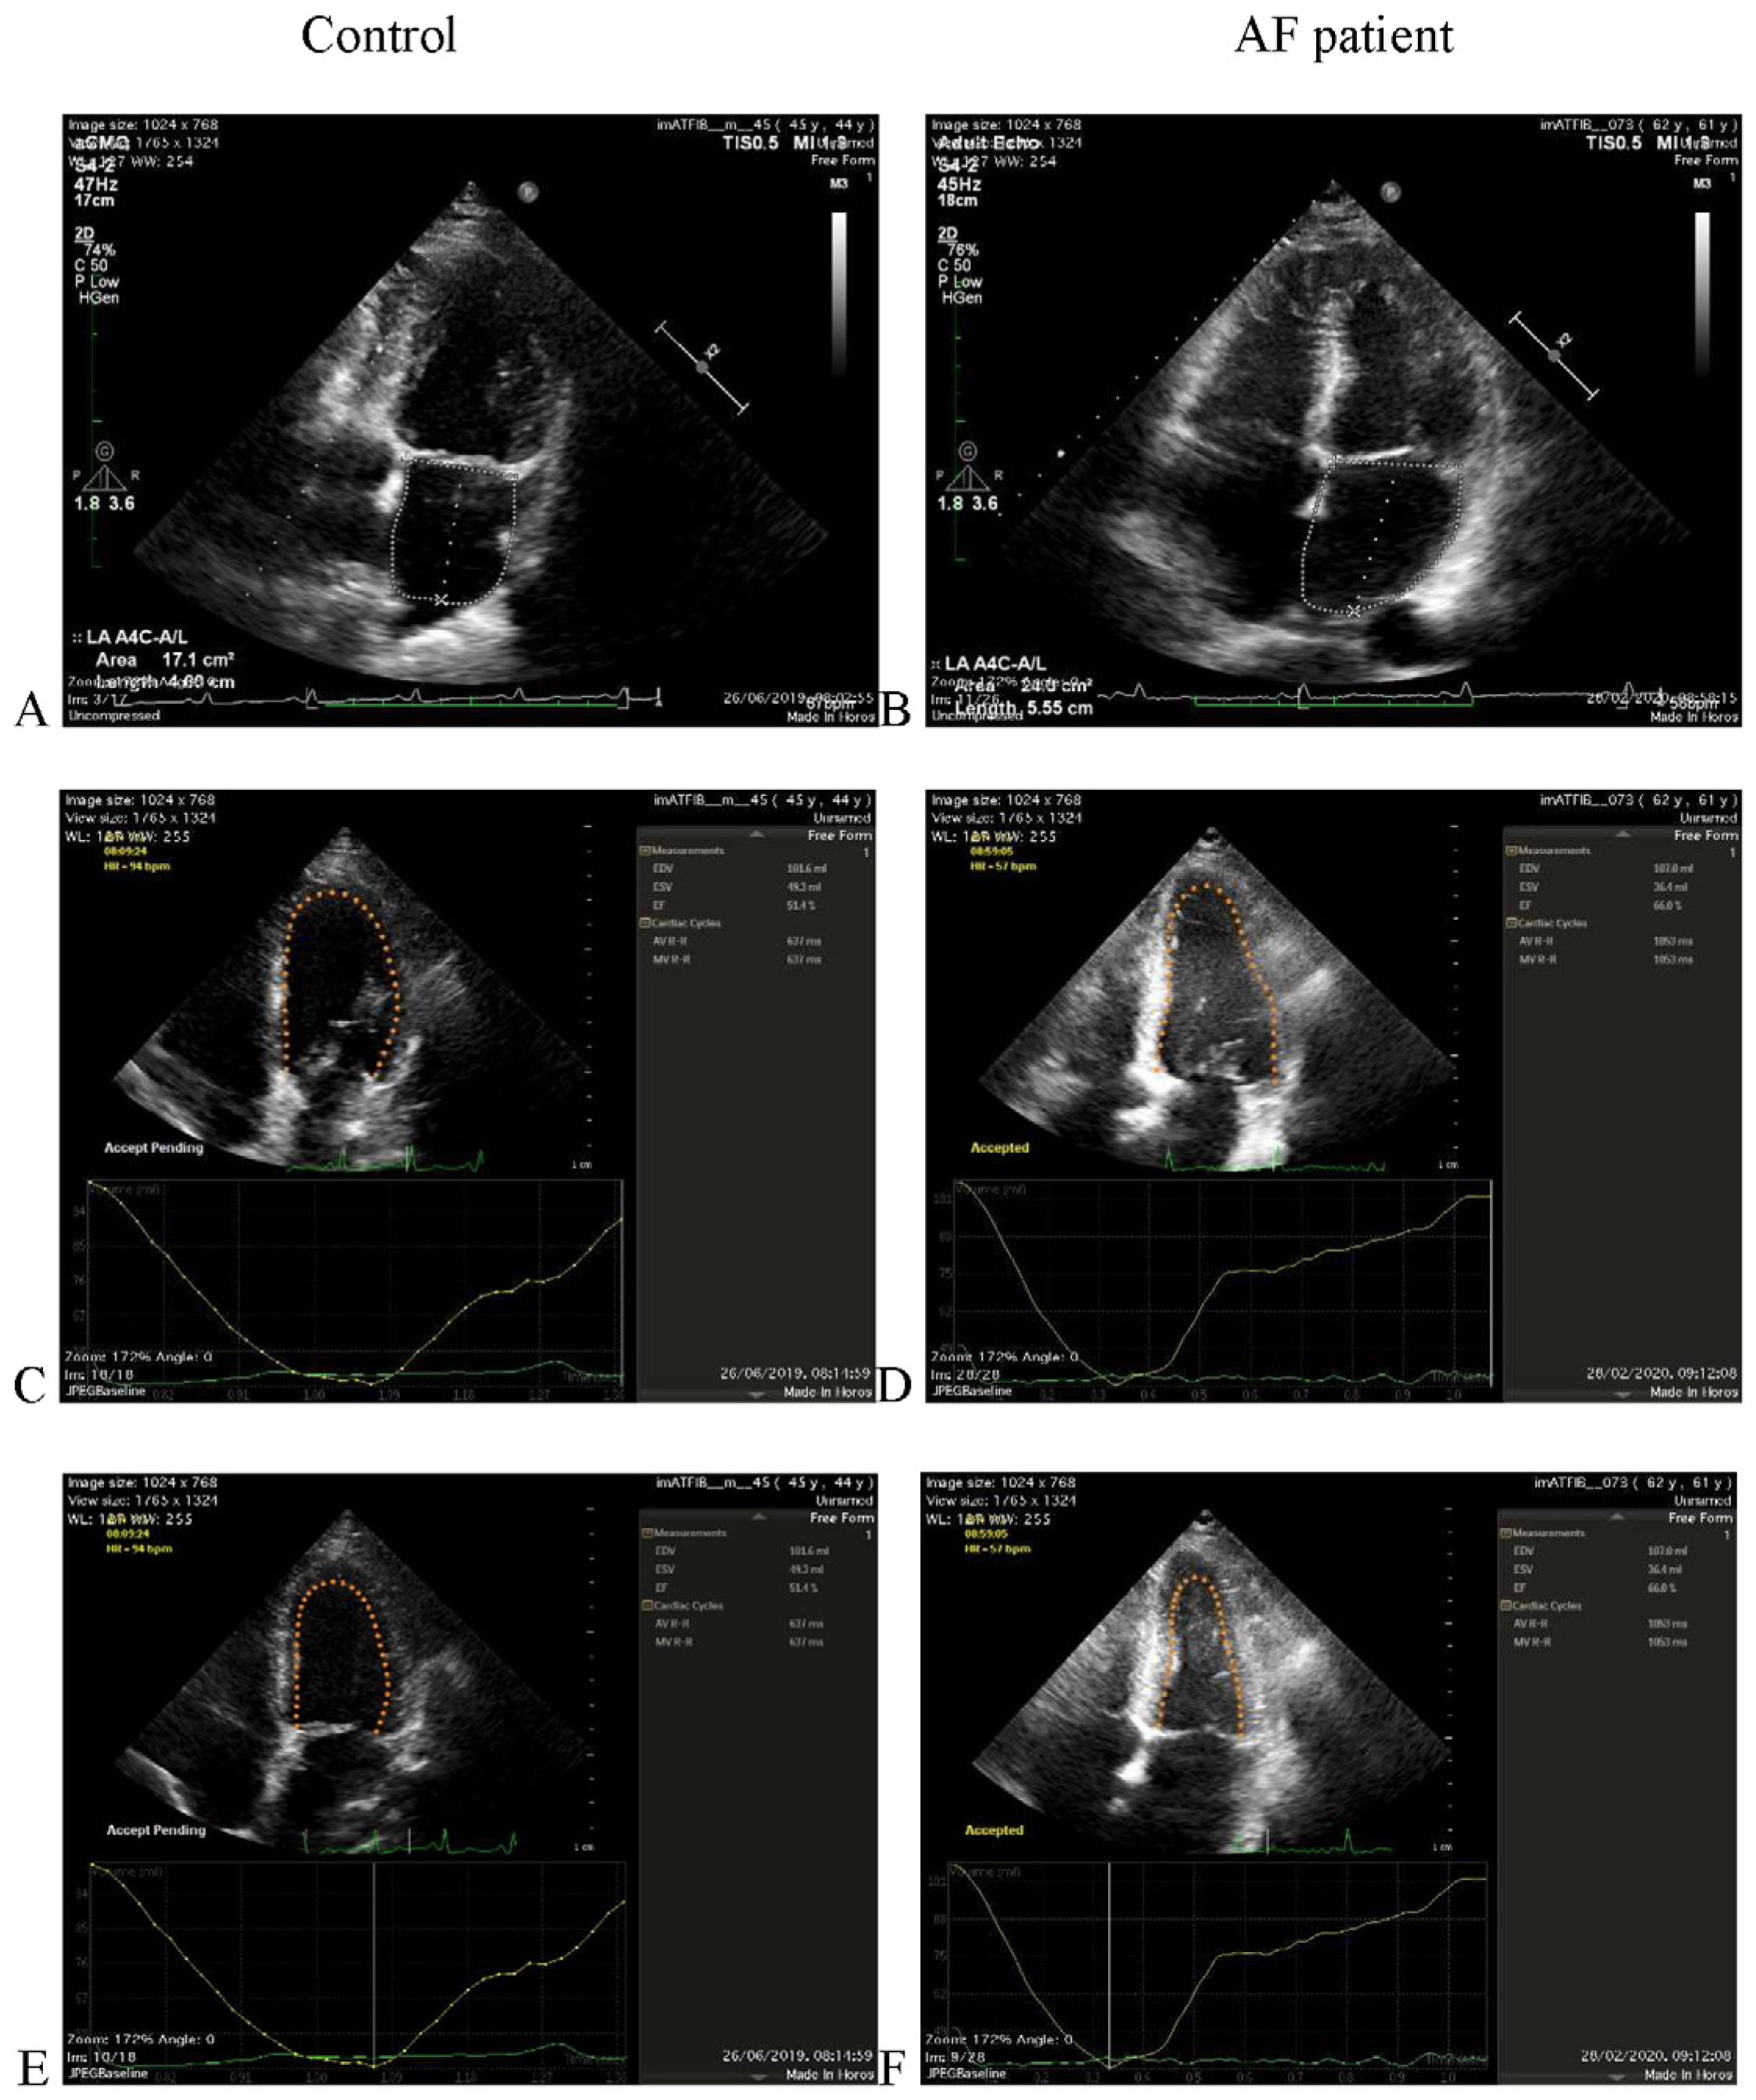

1. Introduction

2. Materials and Methods

2.1. Echocardiographic Acquisition